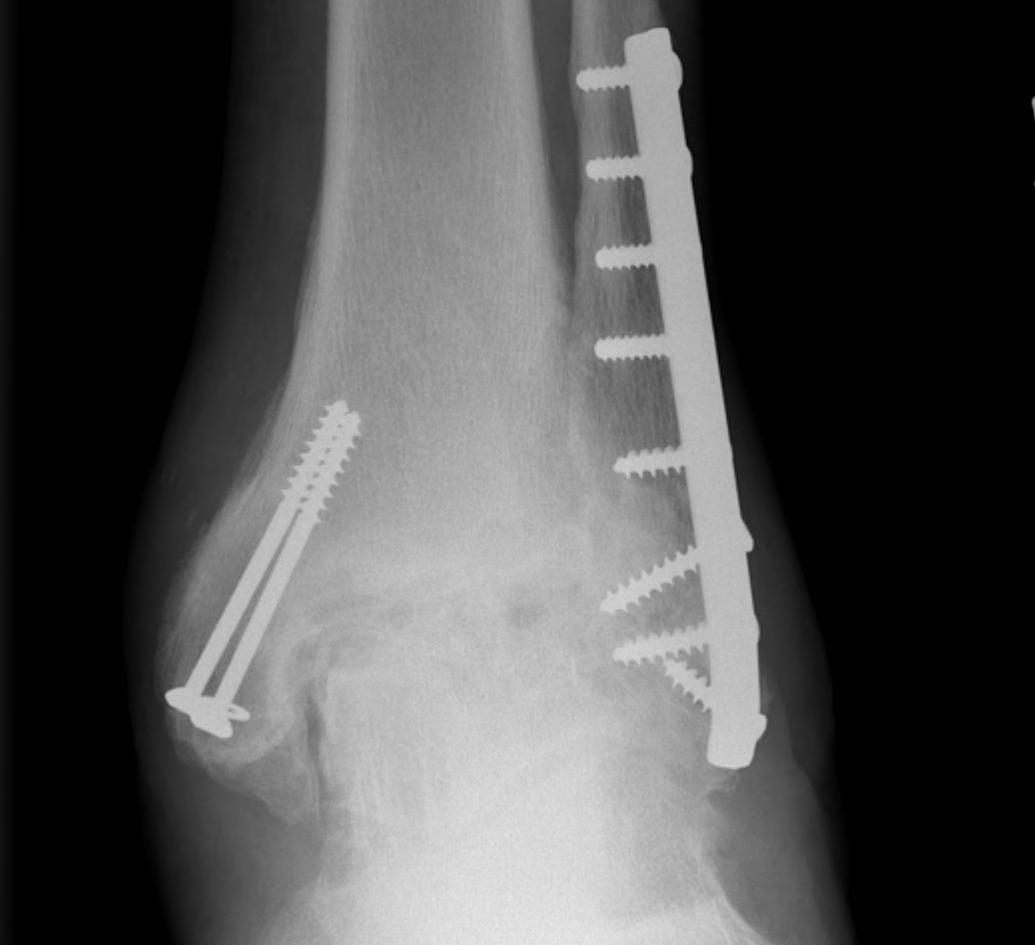

B. Lateral approach and fibular osteotomy

Zimmer Biomet Trabecular Metal PDF

Vumedi fibula osteotomy approach for total ankle arthroplasty